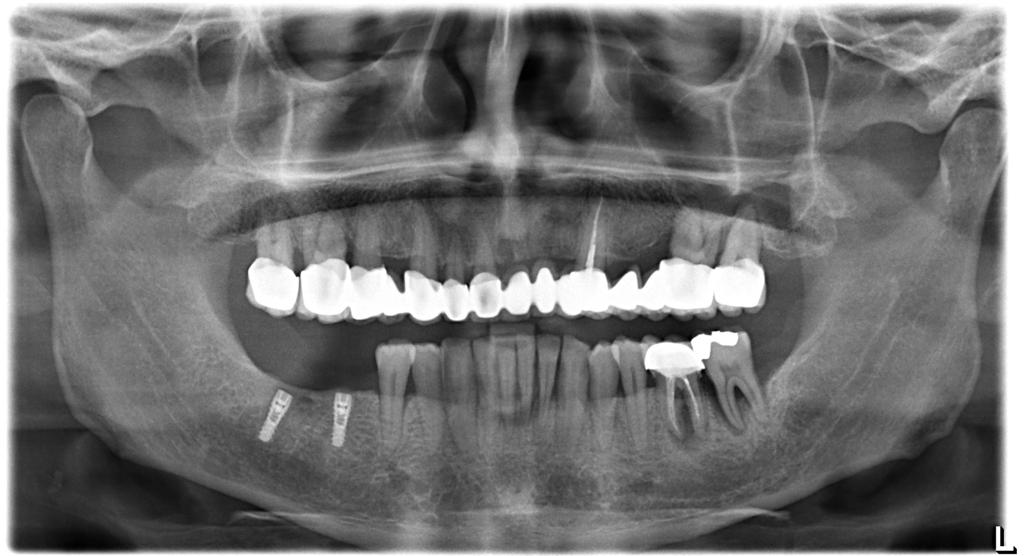

Case Presentation: A 42-year-old male patient with high diabetes and heavy smoking-alcohol use presented with multiple tooth loss. These systemic health factors posed potential risks for implant treatment. However, successful implant placement with Naxis implants was achieved in sites 46-47 to address the patient's dental needs. Approximately two years later, implants were also placed in sites 36-37 using Naxis implants.

Post-Treatment Evaluation: The patient continued smoking and alcohol consumption after implant surgery. However, evaluation of the long-term stability and success rates of the implants, based on X-ray images taken five years later, revealed that the Naxis implants were securely maintained. This demonstrates that successful implant treatment is possible despite the negative effects of systemic health factors, with regular follow-up and periodontal care.